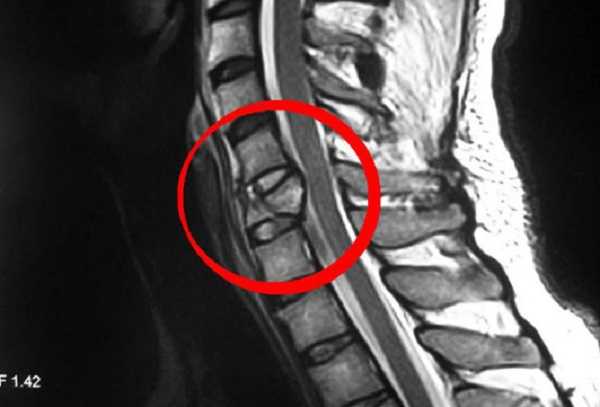

- В качестве дополнительной диагностики назначают магнитно-резонансную томографию, которая поможет визуализировать межпозвоночные грыжи и протрузии.

Если на основе полученных снимков нельзя поставить окончательный диагноз, то будет назначена магнитно-резонансная или компьютерная томография. При наличии сопутствующих заболеваний, провоцирующих защемление нерва в шейном отделе, врач должен провести дополнительное соответствующее обследование. Если в результате заболевания резко ухудшилось зрение, то нужно провести исследование глазного дна.